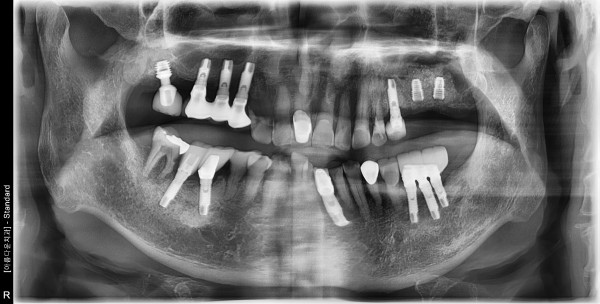

69세남자 좌측상악 상악동거상술및임플란트식립